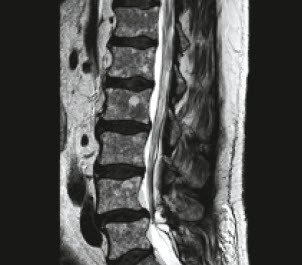

Die Wirbelsäule beheimatet mit dem Rückenmark und den Spinalnerven lebensnotwendige und äußerst sensible Bestandteile des Nervensystems. Eine Wirbelsäulen-OP kann unter anderem bei Krankheitsbildern wie der Skoliose dem Bandscheibenvorfall der Spinalkanalstenose oder Wirbelgleiten notwendig werden. Allgemein werden als Zysten flüssigkeitgefüllte Gebilde bezeichnet die von einer Membran oder Wand umgeben sind.

Wird die Zyste jedoch zu groß oder verursacht Beschwerden sollte sie entfernt werden. Die Computertomographie CT wird solchen Zysten im Wirbelkanal Der Autor.